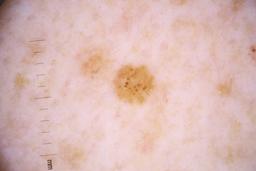

ISIC_4077341

Clinical

| Field | Value |

|---|---|

| acquisition_day | 1 |

| age_approx | 50 |

| anatom_site_1 | Trunk |

| anatom_site_2 | Anterior trunk |

| concomitant_biopsy | False |

| dermoscopic_type | contact non-polarized |

| diagnosis_1 | Benign |

| diagnosis_confirm_type | serial imaging showing no change |

| family_hx_mm | False |

| image_type | dermoscopic |

| lesion_id | IL_9238622 |

| patient_id | IP_1969685 |

| personal_hx_mm | True |

| sex | male |

Columns

Showing first 50 images.